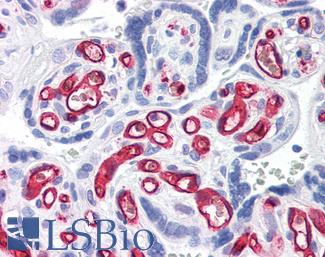

CK7 (KRT7)

Anti-KRT7 / Cytokeratin 7 antibody IHC of human placenta. Immunohistochemistry of formalin-fixed, paraffin-embedded tissue after heat-induced antigen retrieval. Antibody LS-B7164 concentration 10 ug/ml.